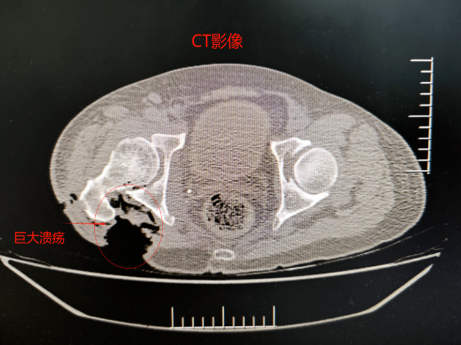

复查CT、MR检查,创面仍在加深,股骨部分已经外露,并且发现右侧腰大肌肿瘤侵犯生长,加之长期营养的消耗,创面暴露合并严重感染,也是治疗中的难点。

患者病情复杂,手术难度大,经院科级讨论,将叶先生的病历资料发至中山大学附属肿瘤医院,请骨肿瘤科朱教授会诊,最终确定手术方案:腰大肌肿瘤切除、右臀部巨大溃疡清创及应用大腿的转移皮瓣来修复整个缺损创面,将臀部的“大窟窿”补起来。经过7个小时的奋斗,手术顺利完成。